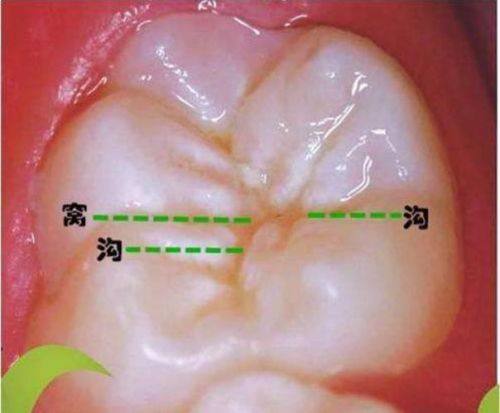

19. 儿童窝沟封闭:100 - 300元